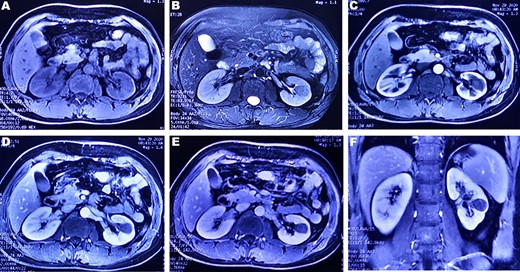

A 37-year-old male underwent a computed tomography scan (CT), which revealed a 2.5 × 1.9 cm slightly lower density ingrown mass in the lower pole of left kidney for 1 month. The patient was asymptomatic and had a history of kidney stones. The shape of the mass was regular, with unclear boundaries. Enhanced CT showed that the enhancement of the mass was lower than that of the surrounding renal parenchyma (Fig. 1). On magnetic resonance imaging (MRI), a circular abnormal signal was detected in the cortical medullary area of left kidney, with an equal signal on T1WI and a slightly low signal on T2WI (Fig. 2A and B). The enhanced MRI scan showed no obvious enhancement in the cortical and medullary phases and a slightly dotted high signal in the excretion phase (Fig. 2C–F). The mass was a space-occupying ingrown lesion with insufficient blood supply. Patients underwent laparoscopic partial nephrectomy and received no postoperative therapy. After the tumor was incised, a 2.3 × 2 cm soft mass that was grayish-white and slightly grayish-yellow was found with clear boundary. Histology (hematoxylin and eosin staining) results showed that the tumor was composed of elongated tubules arranged in parallel. The tubules lined with cuboid and spindle cells set in a small amount of myxoid matrix (Fig. 3A). Most of the tumor cells were round, a few were spindle and elliptical, with eosinophilic nucleoli. Mitotic figures were rare and the atypia is not obvious. Obvious foamy macrophage aggregates could be seen in some areas (Fig. 3B). Immunohistochemical results were as follows: CK7(+), P504S (+), PAX-8(+), CD10(−) (Fig. 3C–F). The Ki67 stain showed proliferation rates up to 5%. The pathological result demonstrated left renal mucin-poor MTSCC. We performed next-generation sequencing (NGS) for case, and the result showed that the tumor mutational burden was 2.74 mutation/Mb. RET gene mutation was considered as a mutation of uncertain significance. The detection of multiple genetic polymorphism sites of tumors shows that it may be slightly sensitive to some chemotherapeutics like gemcitabine. PD-1/PD-L1 immunotherapy may not benefit the patient. The patient was followed up for 8 months after surgery. No evidence of metastasis or recurrence was found.

(A) Many elongated tubular epithelial cells arranged in a small amount of mucus. Some spindle cells can be seen (magnification, ×20); (B) Obvious foamy macrophage aggregates in some areas (magnification, ×10). Immunohistochemical results: (C) CK7(+), (D)P504S (+), (E)Pax-8(+), (F)CD10(−).